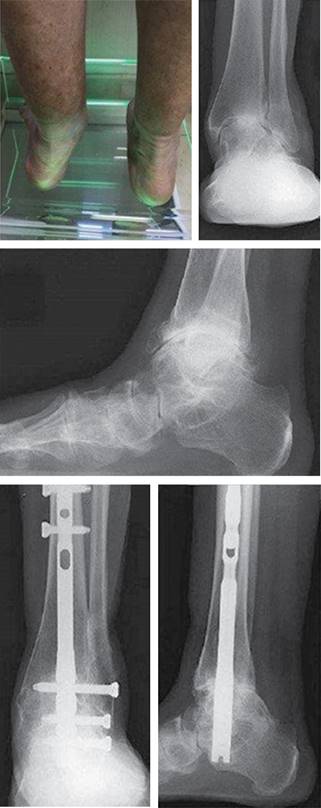

Artrodesis tibio astrágalo calcánea

El desarrollo progresivo en el tiempo de la disfunción supone un tendón degenerado o roto que evoluciona hacia una deformidad que termina afectando prácticamente a todo el pie y se corresponde con el estadio IV.122

La caída del arco longitudinal en este estadio es irreductible, el retropié está en valgo, con insuficiencia del ligamento medial y colapso del astrágalo, con cambios degenerativos artrósicos a nivel de las articulaciones subastragalina, astragaloescafoidea y tibioastragalina.

La deformidad puede ser flexible (estadio IV-A) o rígida (estadio IV-B), según el momento de la evolución y la existencia o no de artrosis.